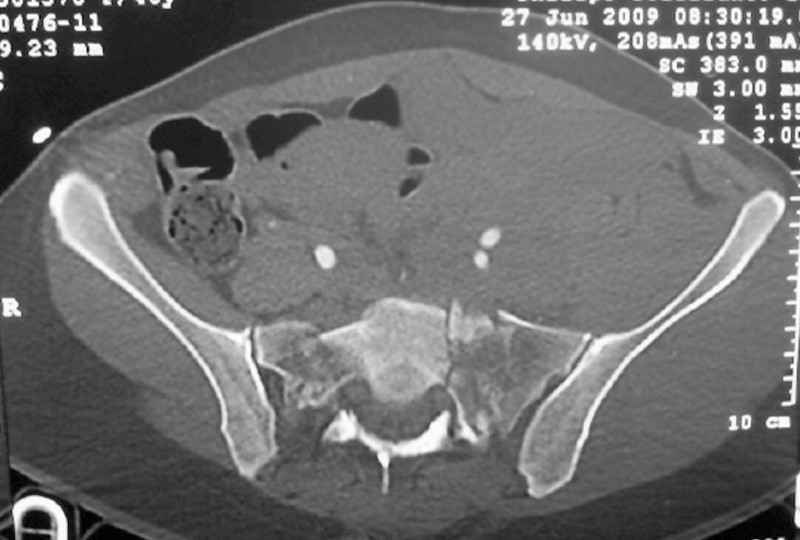

I'm posting this case on behalf of Dr. Pedro Caba, he is unable to post but able to read. 41 yo female , fall from 10 meters five days ago. Hemodynamically unstable on admission treated by angio and embolization and skeletal traction, with no external support. No associated injuries. Based on CT scan the pt has a both column fracture with conminuted dome and displaced anterior column and a sacral Denis 1 fracture with a displaced left ala. I think the best approach for the acetabular fracture is ilioinguinal with Smith-Petersen extension but don't know exactly the sequence . Will you start with the sacral fracture? Which technique? Thanks in advance Pedro Caba Unidad de Trauma Hospital 12 de Octubre Madrid Spain

The soft tissues are also in mild condition, buttock hematoma and probably a Morel-Lavalle. I send some more CT images. There are some conminution in the posterior column (I don’t have images now). The patient is scheduled for surgery next Monday. The plan is percutaneous sacral fixation and then ilioinguinal approach .

This complex and displaced sacral injury is likely an H pattern...2 hemipelvic components, an upper sacral component which remains attached to the lumbar spine, and a caudal sacral component...there are typically anterior ring injuries as well...in this patient's example, the left sided acetabulum also has been exploded.

The hemipelvic components' displacements depend on their instability...this patient's left side seems to be the worst.